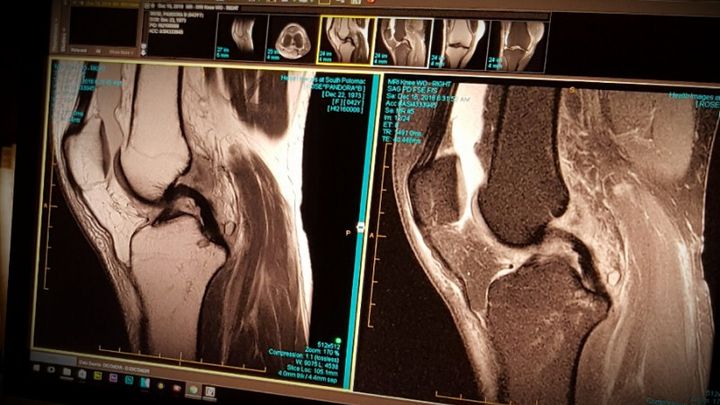

Thankfully, the X-rays showed that I didn’t break any bones. However, the MRI revealed a complete tear of my ACL and lateral Meniscus with partial tears and sprains to the MCL & PCL. I’ve been in moderate pain, on crutches and required to wear a knee brace ever since. Bottom line, I need arthroscopic surgery to replace and repair the ACL & Meniscus. I will be laid up and in therapy for months. As bad as that is, I admit that what’s worse is that, even with insurance, we simply don’t have the money to cover the deductible and co-pays.

Thankfully, the X-rays showed that I didn’t break any bones. However, the MRI revealed a complete tear of my ACL and lateral Meniscus with partial tears and sprains to the MCL & PCL. I’ve been in moderate pain, on crutches and required to wear a knee brace ever since. Bottom line, I need arthroscopic surgery to replace and repair the ACL & Meniscus. I will be laid up and in therapy for months. As bad as that is, I admit that what’s worse is that, even with insurance, we simply don’t have the money to cover the deductible and co-pays.